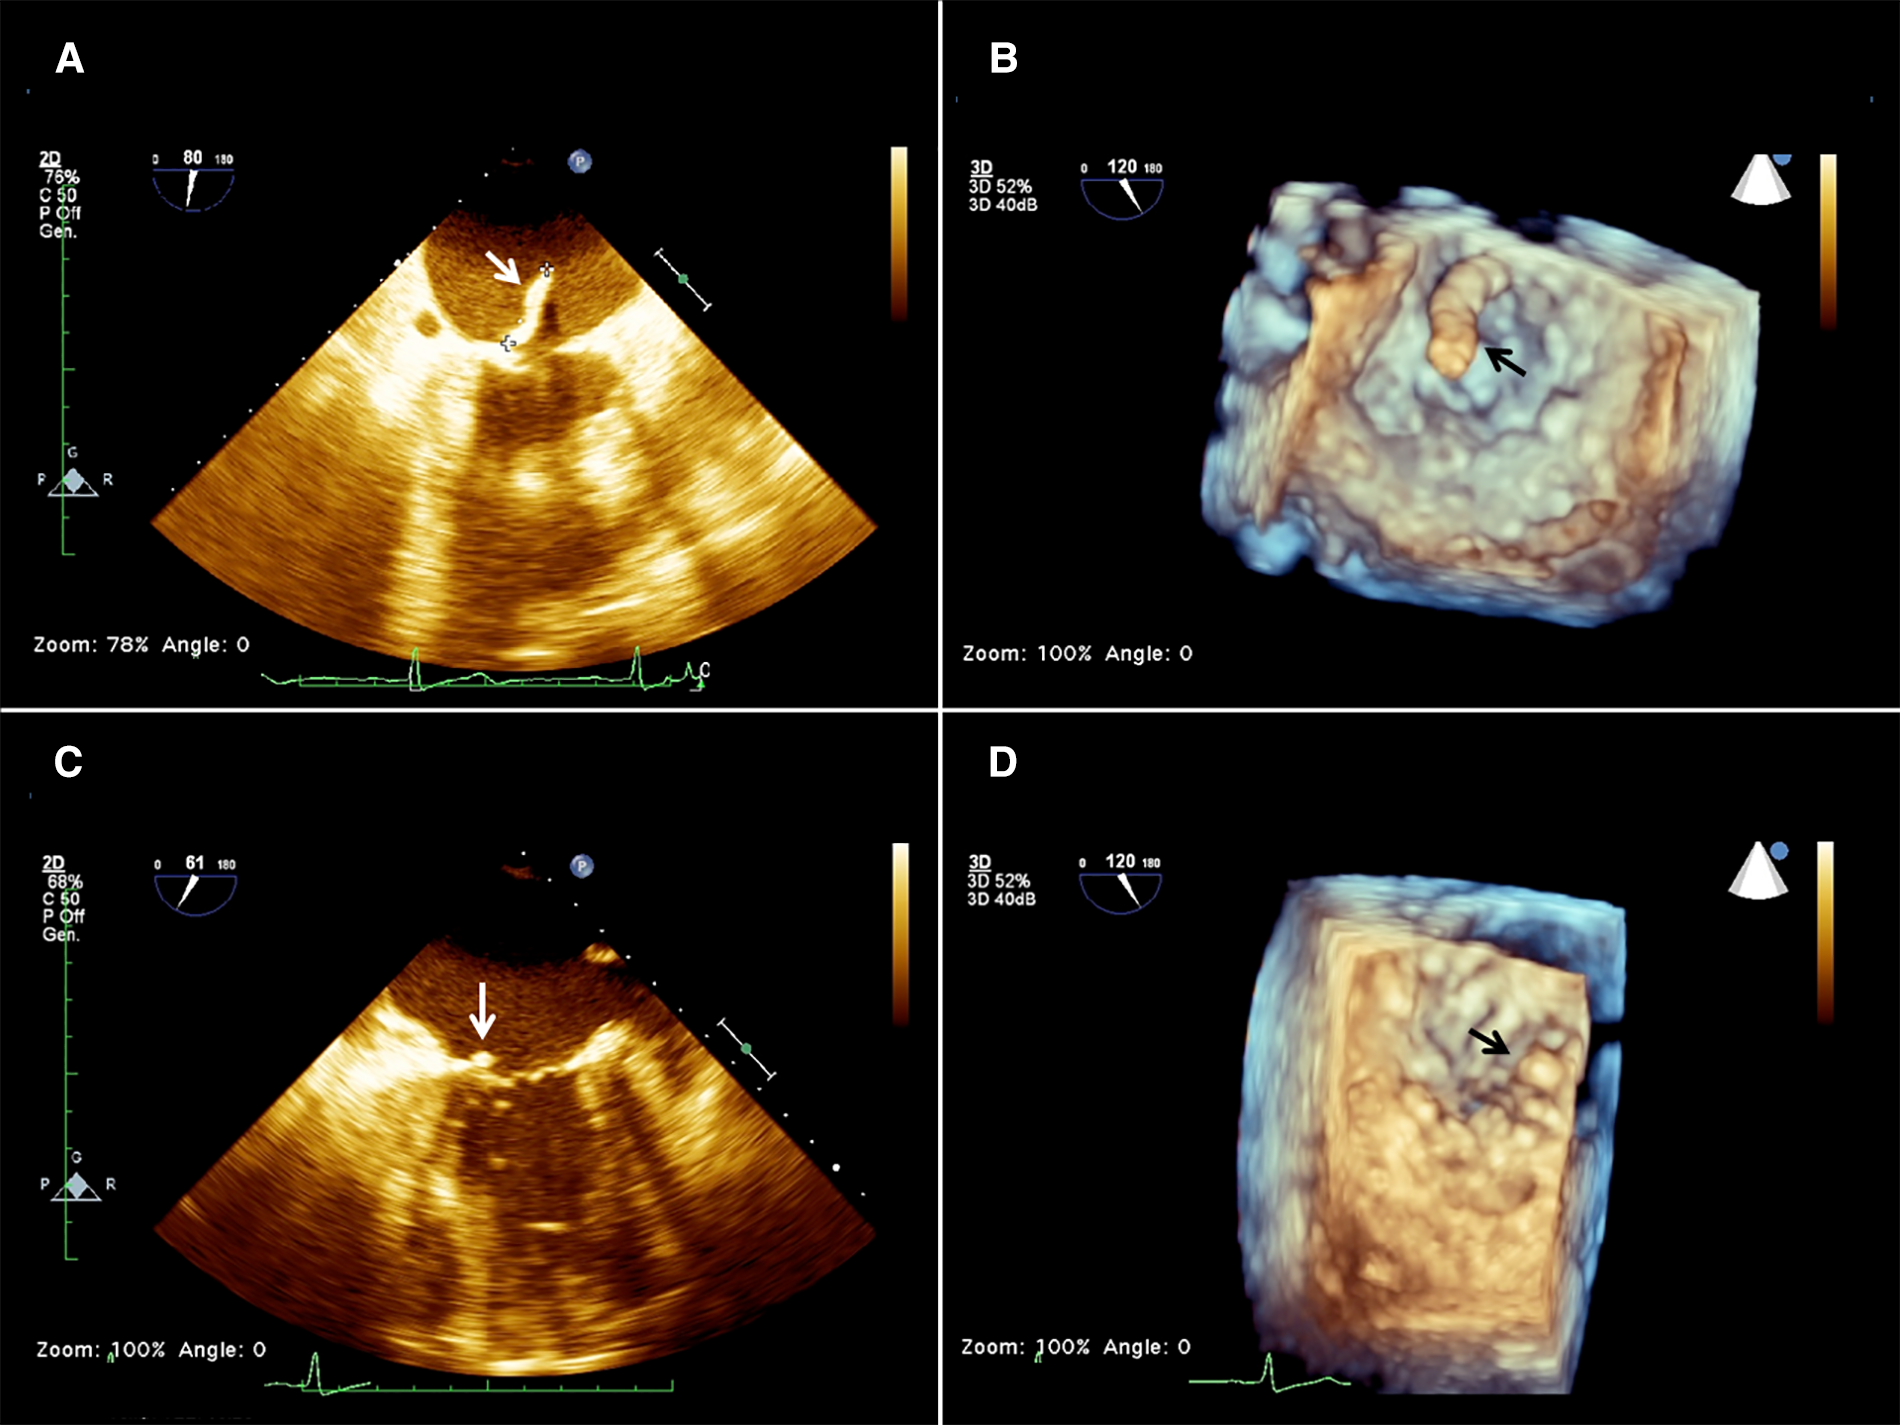

A 57-year-old woman was brought to the emergency room after an incidental fall due to loss of balance. She had a history of insulin-dependent type 2 diabetes complicated with inferior limbs trophic ulcers. She was also on hemodialysis for chronic kidney disease and was being treated for peripheral vasculopathy with right leg arteries and renal arteries stenting. She had severe obesity and was newly diagnosed with a left kidney mass with surgical indications. Her symptoms included bilateral hip pain, exertional dyspnea, fatigue, and drowsiness. Blood tests did not show significant alterations except for anemia, a critical increase in the white cell count (21.80×*103/µl), and inflammatory markers (CRP 19.63 mg/dl and 2.96 ng/ml procalcitonine). Creatinine was 7.47 mg/dl and urea was122 mg/dl. A transthoracic echocardiography (TTE) showed a large floating mass attached to the atrial surface of the posterior leaflet of the mitral valve close to the annular leaflet insertion. The mass freely prolapsed into the ventricular chamber during diastole, showing a mobile behavior and a small implant basis. Mild-to-moderate mitral regurgitation was associated with mass prolapse. These findings were later confirmed by transesophageal echocardiography (TEE), measuring a 20 × 8 mm neoformation (Figures 1A,B).

Figure 1

2d (A) and 3D (B) preoperative transesophageal echocardiography (TEE) showing the presence of a mass (arrow) attached to the base of the anterior mitral leaflet on the atrial aspect of the mitral valve, and 2D (C) and 3D (D) postoperative TEE showing a residual minimal stump (arrow).

Considering her high surgical risk, the patient was accepted for mass aspiration using the AngioVac system. A cerebral embolic protection device TriGuard (Keystone Heart Ltd., Herzliya, Israel) was used before the procedure. The left subclavian artery was exposed and cannulated with a 16 Fr cannula (Biomedicus, Medtronic, Minneapolis, MN, USA) for blood reinfusion. Transapical access was obtained through a left anterolateral mini-thoracotomy at the 5th intercostal space. Two perpendicular pledgeted U-shaped purse strings were placed at the entry site. After full heparinization, to reach an ACT above 450 s, the ventricle was punctured, and an extra-stiff guidewire was inserted in the left ventricle (LV), carefully crossing the MV under real-time bi-plane TEE guidance. A 26 French GORE DrySeal (W.L. Gore & Associates, Newark, DE) was inserted on the guidewire into the left ventricle and was used to advance a 22 French 180 degrees AngioVac aspiration cannula. The circuit was then established by connecting the outflow to the apical suction cannula and the inflow to the subclavian arterial cannula. An oxygenator (Horizon, Eurosets, Medolla, Italy) was interposed in the circuit, distally to the filter and to the centrifugal pump. The AngioVac cannula was maintained below the MV plane, and the suction was initiated till the mass disappeared on the TEE image and only the stump was left (Figures 1C,D). The suction cannula and the sheath were withdrawn from the heart, reinfusion of the blood was completed, the subclavian arterial cannula was removed, protamine was administered, and purse strings were tied. The TriGuard device was finally retrieved from the right femoral artery which was closed using a percutaneous suture-mediated closure system (PercloseProGlide SMC System, Abbot Vascular, CA, USA). The patient remained hemodynamically stable during the whole procedure with minimal blood loss. At extubation time in the operating room (OR) her neurological status was intact and no bowel/limb ischemia was observed. No specimens were available for histologic examination. Since we could not ascertain the true nature of the mass, intravenous antibiotic therapy was carried on for 6 weeks as part of the endocarditis protocol. TTE was performed 1 week after the procedure, and mild mitral regurgitation (MR) and no regrowth of the mass were reported.